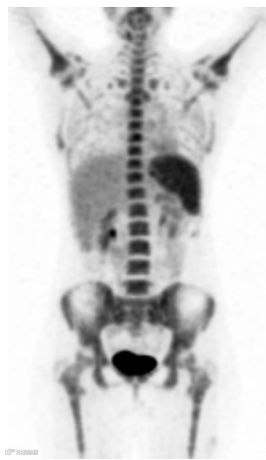

FDG在体内的正常生理积累基于葡萄糖代谢,而葡萄糖代谢是可变的。生理摄取通常可见于脑、心脏、肝、脾、胃肠道、泌尿集合系统(包括膀胱)和骨髓(图1)。

图1. 冠状18F FDG PET 扫描显示脑、心脏、肝脏、脾脏、尿液收集系统(包括膀胱)和骨髓的生理18F FDG 摄取正常。请注意,与身体其他部位的摄取相比,脑部的摄取明显强烈。